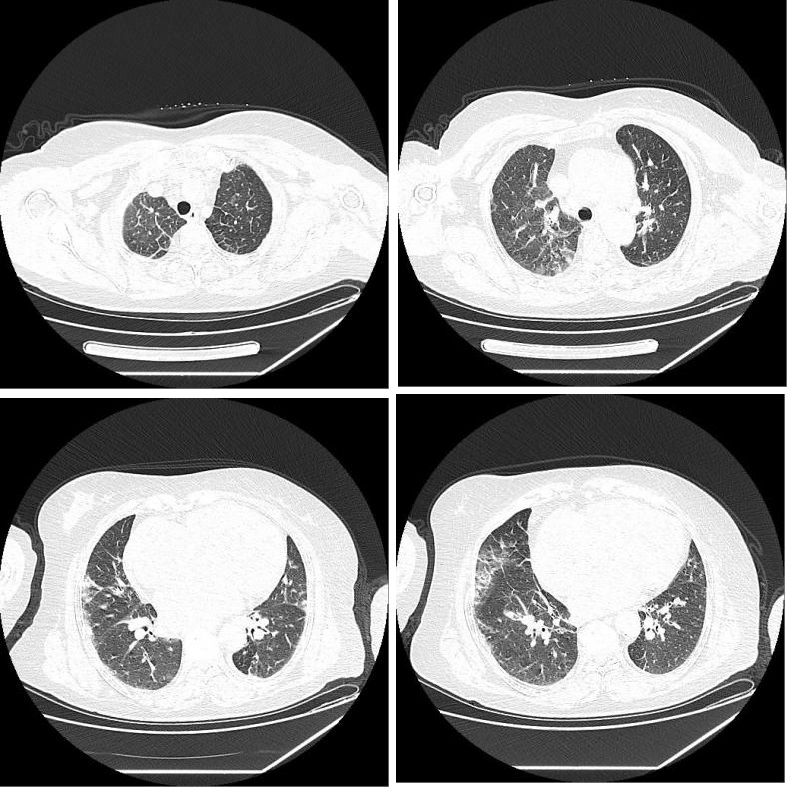

患者女性,71岁,农民,2020年2月6日晚9点左右起夜上厕所时,突发左侧肢体乏力伴口齿不清,摔倒在地,无胸闷、心慌、恶心、呕吐、意识障碍等,后由家人扶至床上观察至次日凌晨3点,症状无明显好转,送至当地医院急诊科,初步诊断为脑卒中,因超过溶栓窗,建议转至上级医院进一步治疗,由急诊120送至江苏省人民医院急诊科就诊,到院后因口罩佩戴不规范,分诊护士指导正确佩戴口罩后送至急诊内科诊间。入院时(2020年2月7日3时45分),测体温37.1℃,呼吸频率18次/min,心率63次/min,血压199/89 mmHg,血氧饱和度99%。既往“高血压”病史8年,口服“苯磺酸氨氯地平片”降压,血压控制在140/80 mmHg左右,“冠心病”病史8年。仔细询问患者家属,患者及其家属发病前2周内居住在家中,无湖北疫区接触史,无新型冠状病毒人员接触史。查体:查体:神清,精神可,口角歪斜,全身皮肤黏膜完整,无皮疹,结膜无充血,口唇红, 双侧扁桃体无肿大,呼吸平稳,双肺呼吸运动对称,双肺底可闻及少量湿啰音,心律不齐,心音强弱不等。神经系统检查:神清,言语欠清,定向力、记忆力、计算力正常,查体合作。颈软无抵抗,双侧额纹对称,双瞳等大等圆,对光反应灵敏,眼球各向运动正常,无明确眼震。左侧鼻唇沟变浅,口角右偏,伸舌左偏。左侧肢体肌张力减低,左上肢肌力Ⅲ级、左下肢肌力Ⅲ级,右侧肢体肌张力正常,右上肢肌力Ⅳ+级、右下肢肌力Ⅳ级。生理反射对称存在,左侧巴氏征阳性。NIHSS 6分。辅助检查:血常规:白细胞4.7×109/L、中性粒细胞3.42×109/L、淋巴细胞计数0.8×109/L、淋巴细胞百分比17%,其余未见明显异常。降钙素原 < 0.1 ng/mL、脑钠肽1 090 pg/mL。心肌标志物、降钙素原、凝血四项及D-二聚体未见明显异常。头颅CT(图 1),胸部CT(图 2)。

| 图 1 右侧放射冠梗死灶 |